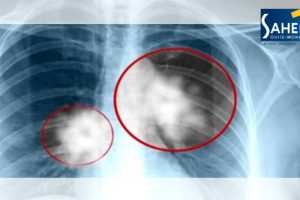

عندما نسمع عن سرطان الرئة، يتبادر إلى الذهن سريعا تدخين السجائر كمسبب رئيسي، لكن العلماء وجدوا أيضا أن بعض الأغذية يمكن أن تؤدي إلى هذا المرض الخطير. وأظهرت...